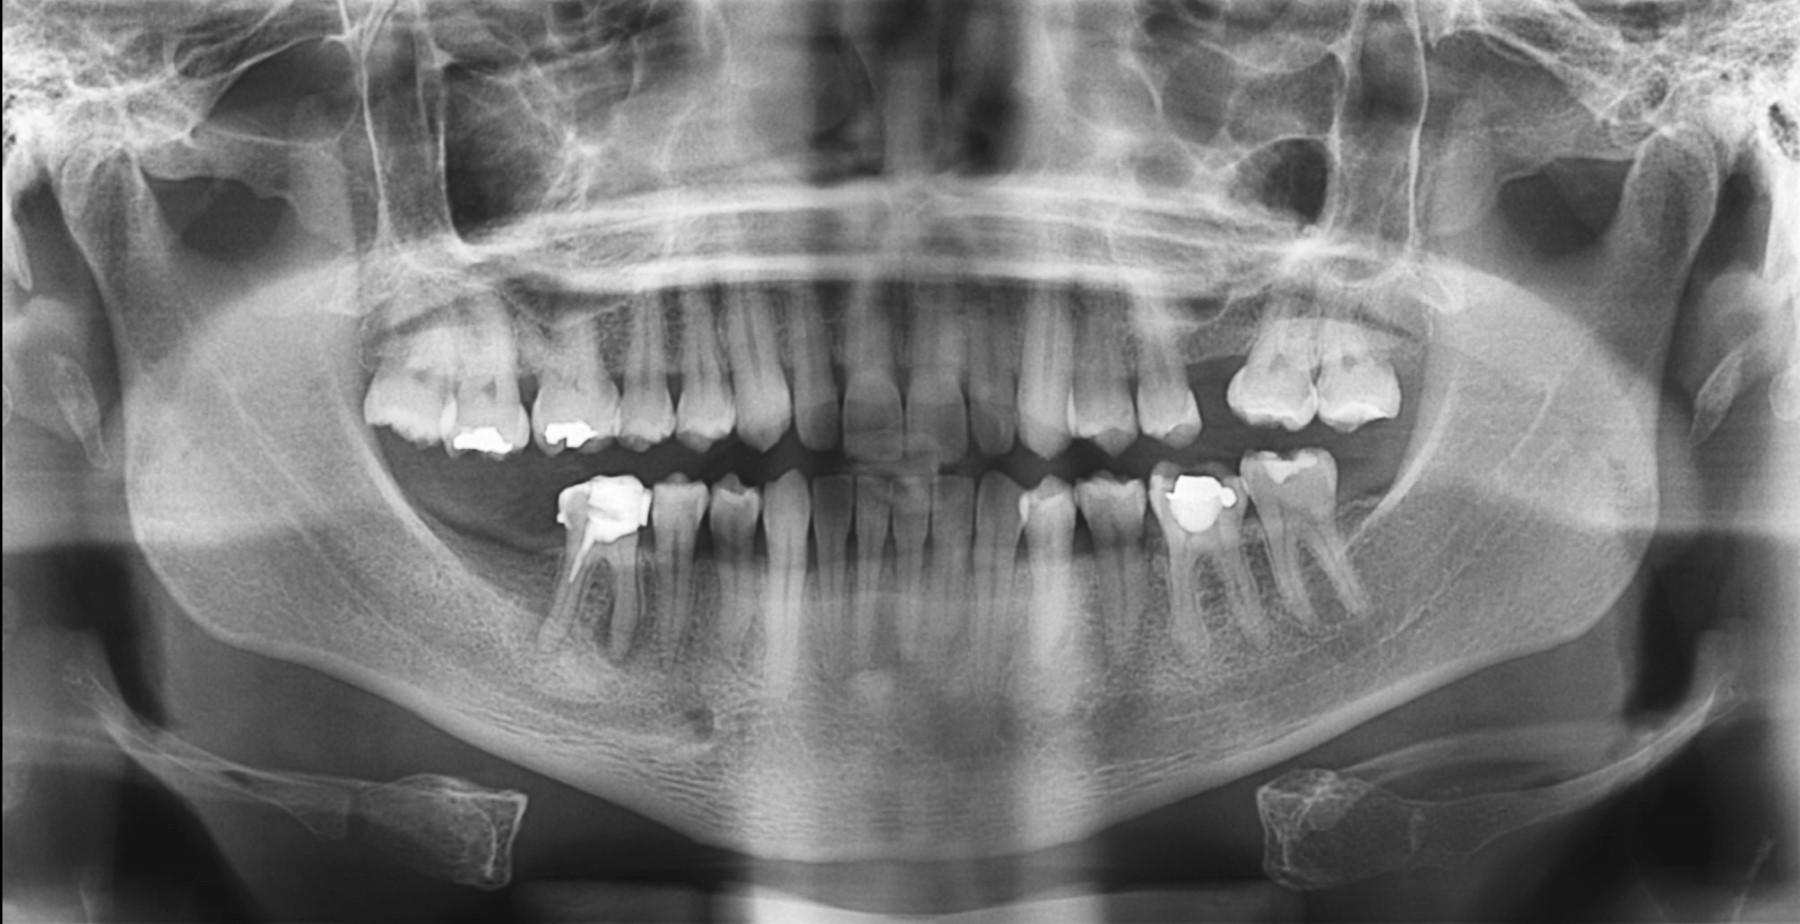

Por otra parte, al correlacionar las variables se encontró que hay variables que contribuyen en mayor proporción a la clasificación de una radiografía como deficiente, tales como: mentón hacia arriba, paciente demasiado hacia atrás e imágenes fantasmas, como se aprecia en el Figura 1.

Podemos observar una estrecha correlación entre paciente hacia atrás e imagen fantasma, por lo que advertimos que ambas ocurren de manera repetida y simultánea r = 0.210 (Figura 2).

Se debe destacar que los diferentes tipos de errores no contribuyen de manera uniforme en la clasificación de una radiografía como aceptable o inaceptable para diagnóstico. Las variables que contribuyen principalmente a la clasificación de una radiografía como inaceptable son: mentón hacia arriba, imagen fantasma, mentón hacia abajo, paciente hacia atrás y hacia adelante, como se puede constatar en la Figura 3.

Un estudio realizado por Yagiz y Ünsal12 en 2021, el cual usa el mismo equipo que el de la presente investigación (Digital Panoramic X-ray system PAX 400), muestra en un reporte de caso las mismas imágenes fantasmas de molares que se observaron en este estudio, descartando un diagnóstico errado de un molar impactado en el seno maxilar, al tratarse de una imagen fantasma tras confirmar con una tomografía computarizada de haz cónico. Demostrando que no siempre es evidente las diferencias entre imágenes reales y fantasmas de molares,12 pues a medida que se desarrollan nuevas tecnologías, los receptores mejoran y la resolución de las imágenes de ortopantomografía aumenta, pudiendo ocasionar que las imágenes fantasmas presenten bordes más definidos y menor distorsión. La alta prevalencia de imágenes fantasmas parece estar relacionada con la malposición de los pacientes, en particular con el del paciente hacia atrás por alguna característica específica del equipo Digital Panoramic X-ray system PAX 400, que hace más frecuente dicho error.